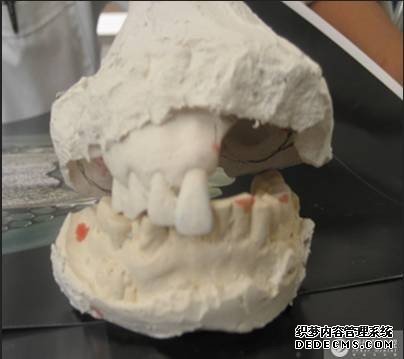

取牙颌模型

义齿加工成型

义齿加工成型